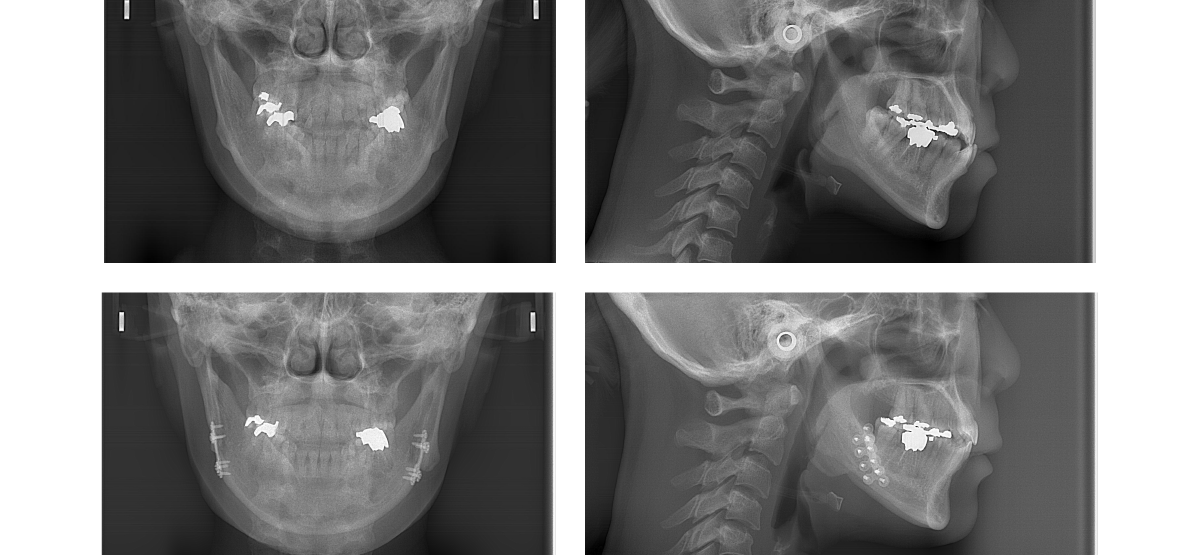

②顎矯正手術(外科矯正)の矯正治療例(30代女性・治療期間2年5か月)

| 年齢・性別 | 30代女性 |

| 治療期間 | 2年5か月 |

| 抜歯 | 上2本(小臼歯) |

| 治療費 | 100万円(調整費、保定費まで含む総額制) |

| 備考 | 裏側矯正 |

| リスク・副作用 | 痛み・治療後の後戻り・歯根吸収・歯髄壊死・歯肉退縮 |

横浜市からご来院の30代女性で、受け口(反対咬合)と交叉咬合(すれ違い)の症状がありました。

治療法は裏側矯正(舌側矯正)で、治療期間は2年5か月です。

2本抜歯で矯正治療を行い、キレイな歯並びになりました。